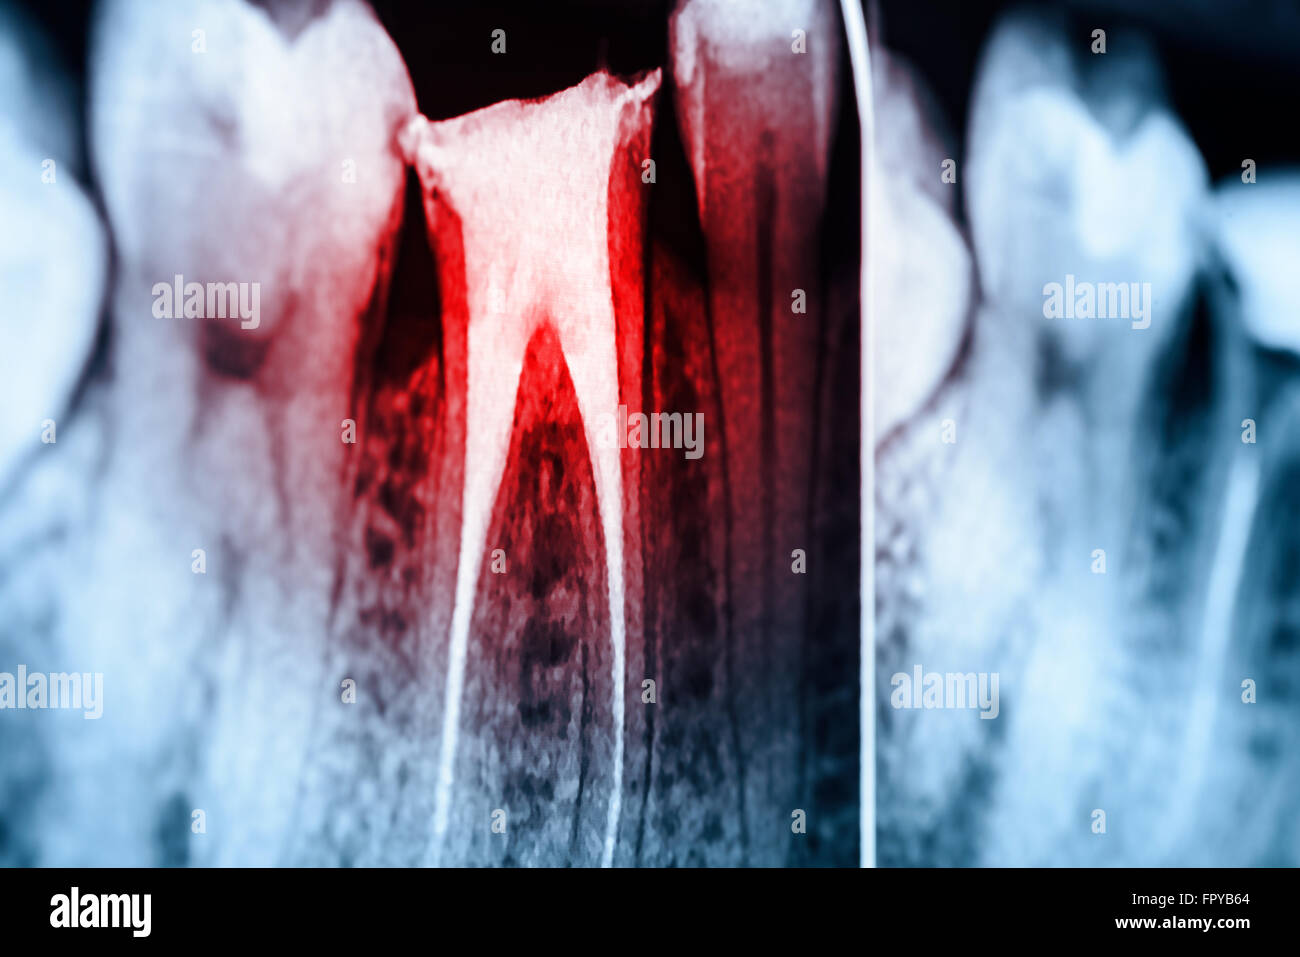

Full Obturation of Root Canal Systems On Teeth XRay Stock Photo Alamy Root Canal Obturation Xray Constriction —the narrowest point of the canal (usually located within 2 mm of the anatomic apex). Ct image shows root canal obturation and extrusion of the root canal sealer in the periapical area of the maxillary central incisor (black arrows). The faculty of general dental practitioners 1 recommends that all root treated teeth should have radiographs taken immediately. Additionally, during. Root Canal Obturation Xray.